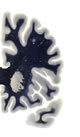

Hi-Resolution Sections · Cells (Nissl Staining) · Virtual Microscopy

Frontal sections (Nissl) from the Atlas Brain: Gallery Slice Single